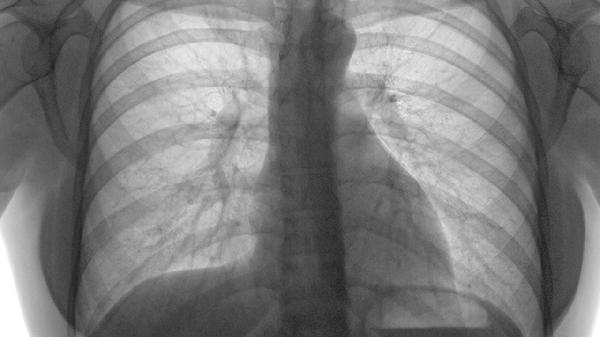

肋间肌劳损通过体格检查排除骨折即可诊断,影像学多无异常。肋软骨炎需结合超声或MRI检查,可见软骨增厚或周围软组织水肿,X线检查主要用于排除其他骨性疾病。